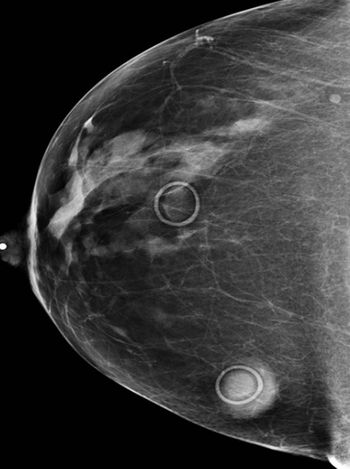

Image IQ: 47-year-old with Multiple Moles, Screening Mammogram

ByMatthew Minn, MD,Erini Makariou, MD

February 12th 2014

• Image IQ: 47-year-old with Multiple Moles, Screening Mammogram

Published: February 12th 2014 | Updated: